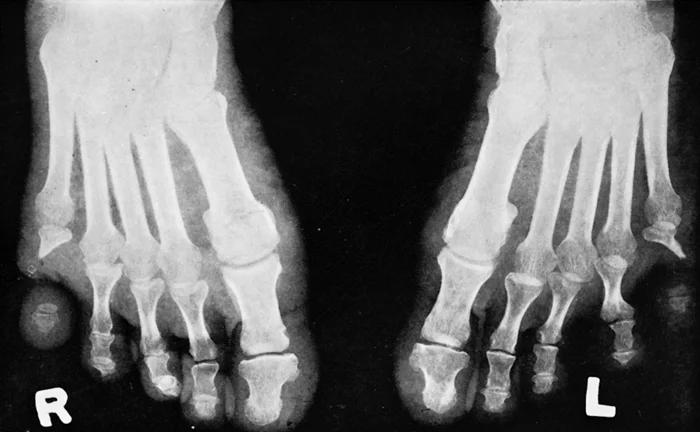

5. Самопроизвольная ампутация

Пожалуй, самое жуткое осложнение ВНБ – это аутоампутация. Что это такое? Это когда из-за повторяющихся травм повреждаются кровеносные сосуды, ткани начинают отмирать, и конечность… просто отпадает. Для людей с ВНБ – это реальная угроза. Пальцы рук и ног страдают чаще всего. И это не самое страшное. Повреждения могут быть гораздо серьезнее, вплоть до потери целой конечности.